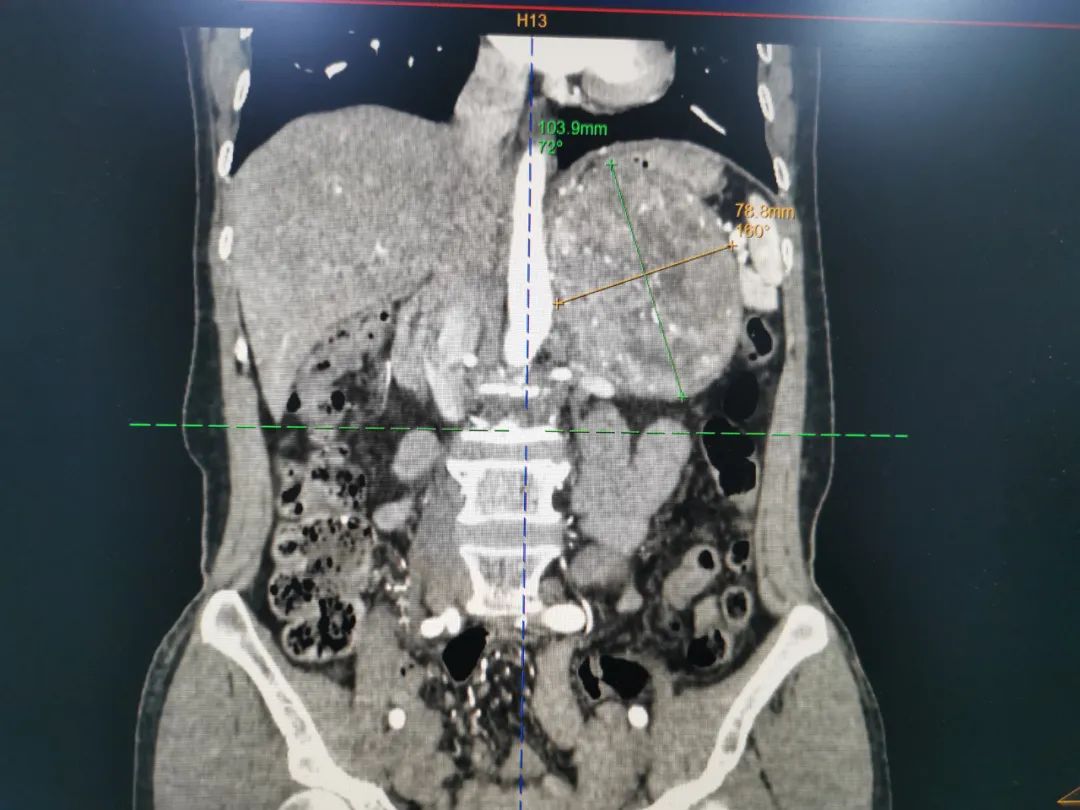

患者龙女士于今年 10 月因发现西瓜大小(13*10 cm)的巨大左侧腹膜后占位入住桂林医学院第二附属医院泌尿外科,经过泌尿外科检查后提示:肾上腺素(epinephrine)和去甲肾上腺素(norepinephrine)这两种儿茶酚胺激素均偏高,考虑为嗜铬细胞瘤可能性大,影像学提示肿瘤巨大,压迫脾脏、胰腺、左侧肾脏等重要器官,临近腹主动脉、脾动脉、肾动脉及肠系膜上动脉等。